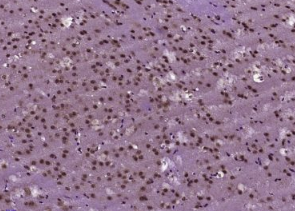

​多聚甲醛固定,石蜡包埋(小鼠脑);用柠檬酸钠缓冲液(pH6.0)煮沸15min后获得抗原;用3%过氧化氢阻断内源过氧化物酶20分钟;阻断缓冲液(正常山羊血清)37℃30min;用(BNC1)多克隆抗体进行抗体孵育Tibody,未结合,1:400,4°C下过夜,然后根据SP试剂盒(兔子)说明和DAB染色进行操作。